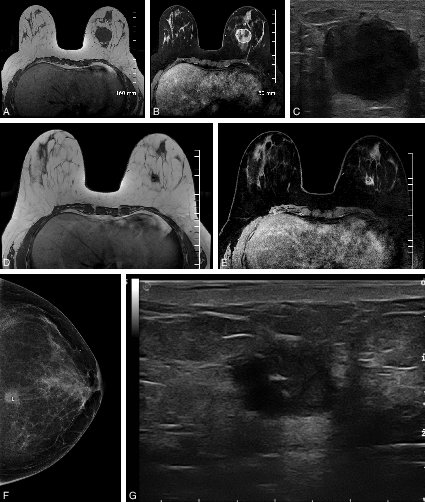

Figure 20.13 Intérêt de l’IRM en cas de chimiothérapie néoadjuvante

Figure 20.13 Intérêt de l’IRM en cas de chimiothérapie néoadjuvante.

A, B, C. Bilan d’imagerie avant chimiothérapie néoadjuvante. D, E, F, G. Bilan d’imagerie en fin de chimiothérapie, avant la chirurgie.